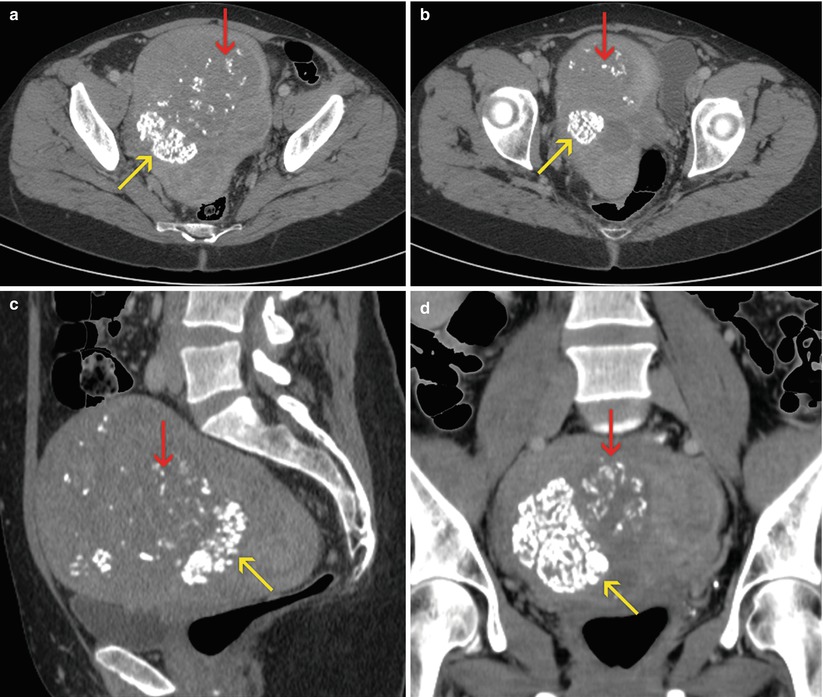

From radiologykey.com

Uterine Wall Pathology Radiology Key What Is Thickening Of The Uterus Wall Called Learn about the types, risk factors,. Endometrial hyperplasia is the thickening of the uterine lining, often caused by hormonal imbalance. It can lead to unusual bleeding and increase the risk of uterine cancer. Find out what normal and abnormal endometrial. Endometrial hyperplasia is a thickening of the uterine lining due to a hormonal imbalance, usually too much estrogen and not. What Is Thickening Of The Uterus Wall Called.

Uterine Wall Pathology Radiology Key What Is Thickening Of The Uterus Wall Called Schink points out, it can eventually lead to malignancy. Endometrial hyperplasia is a condition in which the lining of your womb becomes too thick due to hormonal imbalance. It can be simple or. This is thickening of the uterine lining and it is not always a sign of cancer, even though, as dr. Endometrial hyperplasia is a precancerous condition in. What Is Thickening Of The Uterus Wall Called.